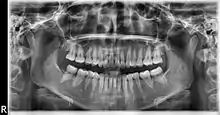

La ortopantomografía o radiografía panorámica es una técnica radiológica que representa, en una única película, una imagen general de los maxilares, la mandíbula y los dientes. Por tanto, es de primordial utilidad en el área dentomaxilomandibular.

Su papel en el diagnóstico odontológico, no solo de los dientes sino también del maxilar y mandíbula, es fundamental. Sin la ortopantomografía, el odontólogo perdería una gran ayuda en la mayoría de las especialidades de su campo. Prácticamente, es utilizada de forma sistemática en odontología, llegando a ser un arma diagnóstica rutinaria. El valor diagnóstico de la ortopantomografía en cirugía bucal, implantología, ortodoncia, periodoncia y en patología oral y dental está claramente demostrado.

El término de radiografía panorámica es el más comúnmente utilizado, ya que la radiografía resultante muestra una visión panorámica de la cara y parte inferior de la cabeza. Laudenback describe la ortopantomografía como uno de los inventos radiológicos más originales de los últimos decenios. El 40 % de los hallazgos patológicos principales y secundarios se descubren a partir de ella. Amplía el campo de diagnóstico en un 70 % y reduce la dosis de radiación de la superficie cutánea en un 90 % con respecto a las series radiográficas periapicales.